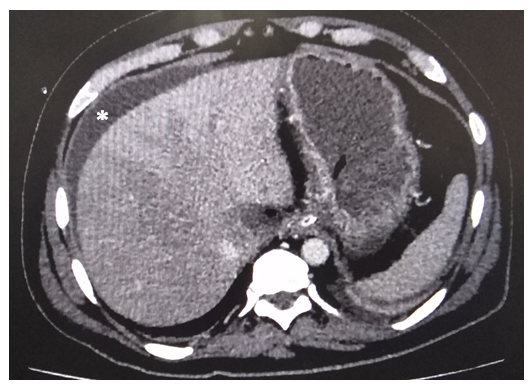

CT Imaging of Pancreatitis and its Complications

Farheen Raza and Muhammad Mobeen